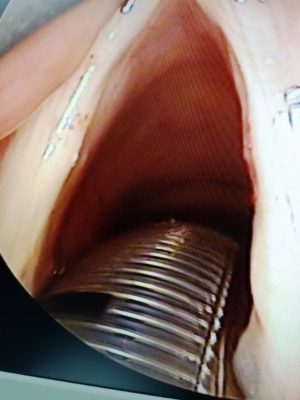

- Phẫu thuật u lành tính thanh quản được thực hiện như thế nào?

4.1 Gây mê

Thủ thuật gây mê trong mổ u thanh quản là gây mê nội khí quản. Nếu như u to và có hiện tượng khó thở, cần phải chọc hút để giảm bớt thể tích trước khi gây mê. Trái lại, nếu như khối u nhỏ, đáy lưỡi không quá dày, bệnh nhân có thể chỉ cần gây tê tại chỗ.

4.2 Các kỹ thuật được thực hiện trong mổ u lành tính thanh quản

- Soi thanh quản bằng bộ soi chuyên dụng để bộc lộ rõ khối u thanh quản.

- Sử dụng các dụng cụ vi phẫu để loại bỏ khối u.

- Kiểm tra, cầm máu bằng đông điện đơn cực (hoặc lưỡng cực).

Hiện nay khoa Tai Mũi Họng- Bệnh viện Quân y 17 đã phẫu thuật thành công nhiều ca u lành tính thanh quản bằng phương pháp nội soi vi phẫu thanh quản, được thực hiện bởi các bác sỹ chuyên khoa TMH có nhiều năm kinh nghiệm, trả lại giọng nói trong và sự hài lòng cho bệnh nhân và người nhà bệnh nhân.